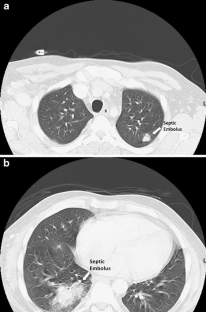

Figure 2